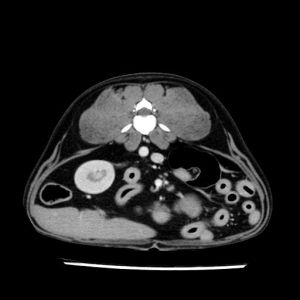

La lesione focale epatica , la ceus,la Tac e il chirurgo .